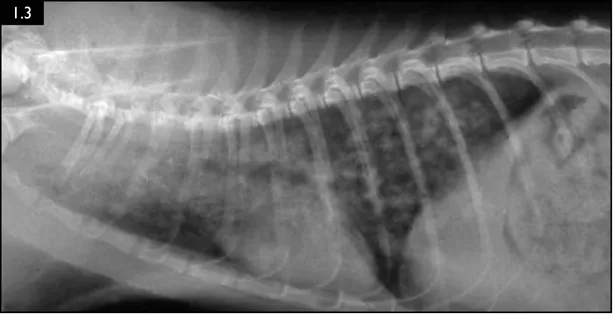

Diagnosis is most often based on detection of larvae in feces via the Baermann technique. The larvae are approximately 360–400 μm in length and the tail ends in a kink with a dorsal subterminal spine (Fig. 1.1). Fecal floatation is less sensitive than Baermann testing, with zinc sulfate flotation having a higher yield than sucrose flotation. Thoracic radiographs are usually unremarkable, but a nodulointerstitial pattern can be present in severe cases (Fig. 1.3).

Fig. 1.3 Radiograph of a feline patient with a severe A. abstrusus infection. (Courtesy of Dr Maria Grazia Pennisi)